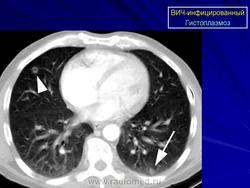

СПИД + гистоплазмоз.

Приложения:

1.g.slayd135.jpg

Histoplasma capsulatum — диморфный гриб, который обнаруживается в основном во влажной почве; вопреки своему названию, он не имеет капсулы. Заболевание эндемично для Юга и Среднего Запада США, а также Центральной Америки и Африки. Вдыхание конидий (спор гриба) может привести к гранулематозному заболеванию у лиц с нормальным иммунитетом. У ВИЧ-инфицированных с иммунодефицитом (у 85% заболевших число лимфоцитов CD4 менее 100 мкл -1) развивается острое угрожающее жизни заболевание с сухим кашлем, лихорадкой, одышкой и слабостью (McKinsey, 1998). В дифференциальной диагностике важное место занимают милиарный туберкулез и пневмоцистная пневмония. Возможна диссеминация инфекции, в этих случаях гриб можно обнаружить к костном мозге и печени (Albrecht, 1994). Описаны случаи язвенного поражения кожи (Calza, 2003; Scheinfeld, 2003).

Гистоплазмоз относится к критериям СПИДа. Чувствительный метод диагностики — выявление антигена в крови. Нередко бывает повышенной активность ЛДГ и ЩФ, а также аминотрансфераз. Начинать лечение следует с амфотерицина B. Липосомный амфотерицин B (3 мг/кг/сут) не только менее токсичен, но и, по некоторым данным, более эффективен (Johnson, 2002). В легких случаях эффективен итраконазол (200 мг 2 или 3 раза в сутки), его можно использовать и для вторичной профилактики. Он существенно эффективнее флуконазола (Wheat, 2002), но вступает в множественные лекарственные взаимодействия, в особенности с ритонавиром (Crommentuyn, 2004). При достаточном восстановлении иммунитета вторичную профилактику гистоплазмоза можно прекратить (Goldman, 2004).